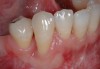

Fig 16. Close-up view of the patient’s gingival architecture following tissue graft healing.

Figure 16